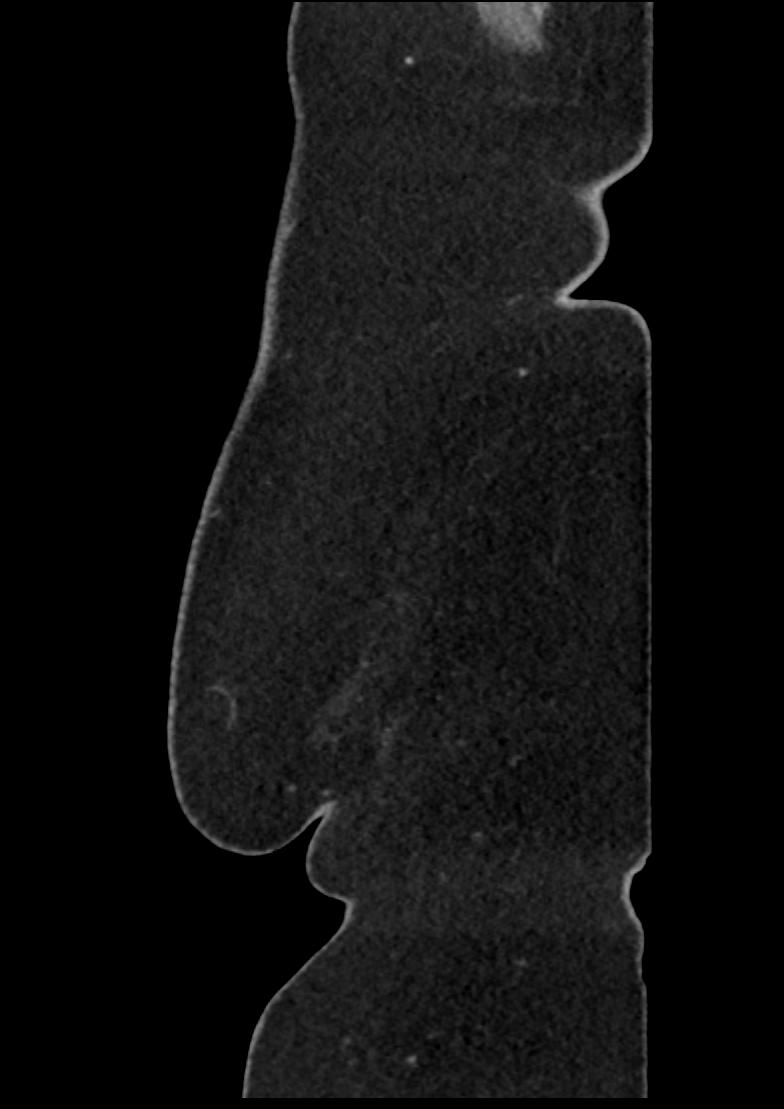

Patient: Padmakumar A. , *1988-04-24, PID: 3000069741773230809

Study Description: CT ABDOMEN

Image Series: Abdomen Sag 3mm [4]

<< Previous | Image 14 of 158 | Next >>